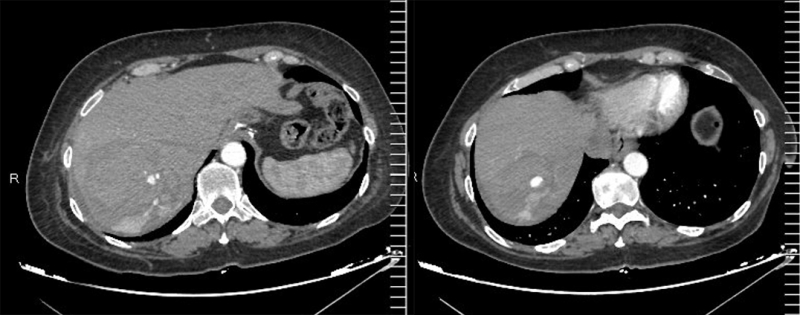

Các bác sĩ tại bệnh viện đã nhanh chóng thăm khám lâm sàng, cận lâm sàng, kết quả siêu âm, CT scanner ổ bụng cho thấy hình ảnh chấn thương gan độ IV, tổn thương đụng dập rách nhu mô phân hạ phân thùy VI,VII,VIII, tổn thương giả phình mạch máu hạ phân thùy VIII, CT scanner ngực có hình ảnh dày tổ chức dày tổ chức kẽ hai phổi, gãy cung trước xương sườn VI bên phải.

Hình ảnh CT scanner ổ bụng của bệnh nhân có chấn thương vỡ gan độ IV